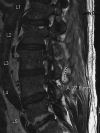

A 54-year-old man with a past medical history significant for sciatica, as well as multiple orthopedic surgeries with hardware, was transferred from an outside rural facility for further workup of a two-month history of progressive back pain and muscle weakness. Investigations ultimately revealed abnormal enhancement from T11 to sacrum, with a large epidural abscess from L5 to the sacrum, best visualized on an MRI. Following the MRI confirmation of loculated complex thoracolumbar abscess, neurosurgery performed a left L3-S1 unilateral laminotomy and evacuation of compressive multiloculated epidural abscesses. The patient was then treated with empirical antimicrobial coverage for epidural abscess with vancomycin and ceftriaxone, which was narrowed to cefazolin based on positive methicillin-susceptible Staphylococcus aureus (MSSA) wound cultures obtained in the operating room. The patient completed a total six-week course of antibiotic therapy. Apart from some superficial wound dehiscence postoperative, the patient ultimately recovered well and had a resolution of most presenting symptoms.